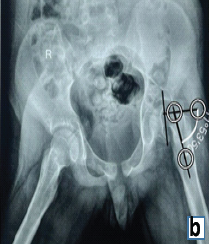

A Race against Time: Managing Acute Unstable Slipped Capital Femoral Epiphysis in a 15-year old with Normal Body Mass Index using the Modified Dunn’s Procedure – A Case Report

Chayapuram Kartheek Reddy , B Mohan Choudhary , J K Giriraj Harshavardhan , Kevin Lourdes , Arjun Ganesh , P Velmurugan

………………………………p.224-228